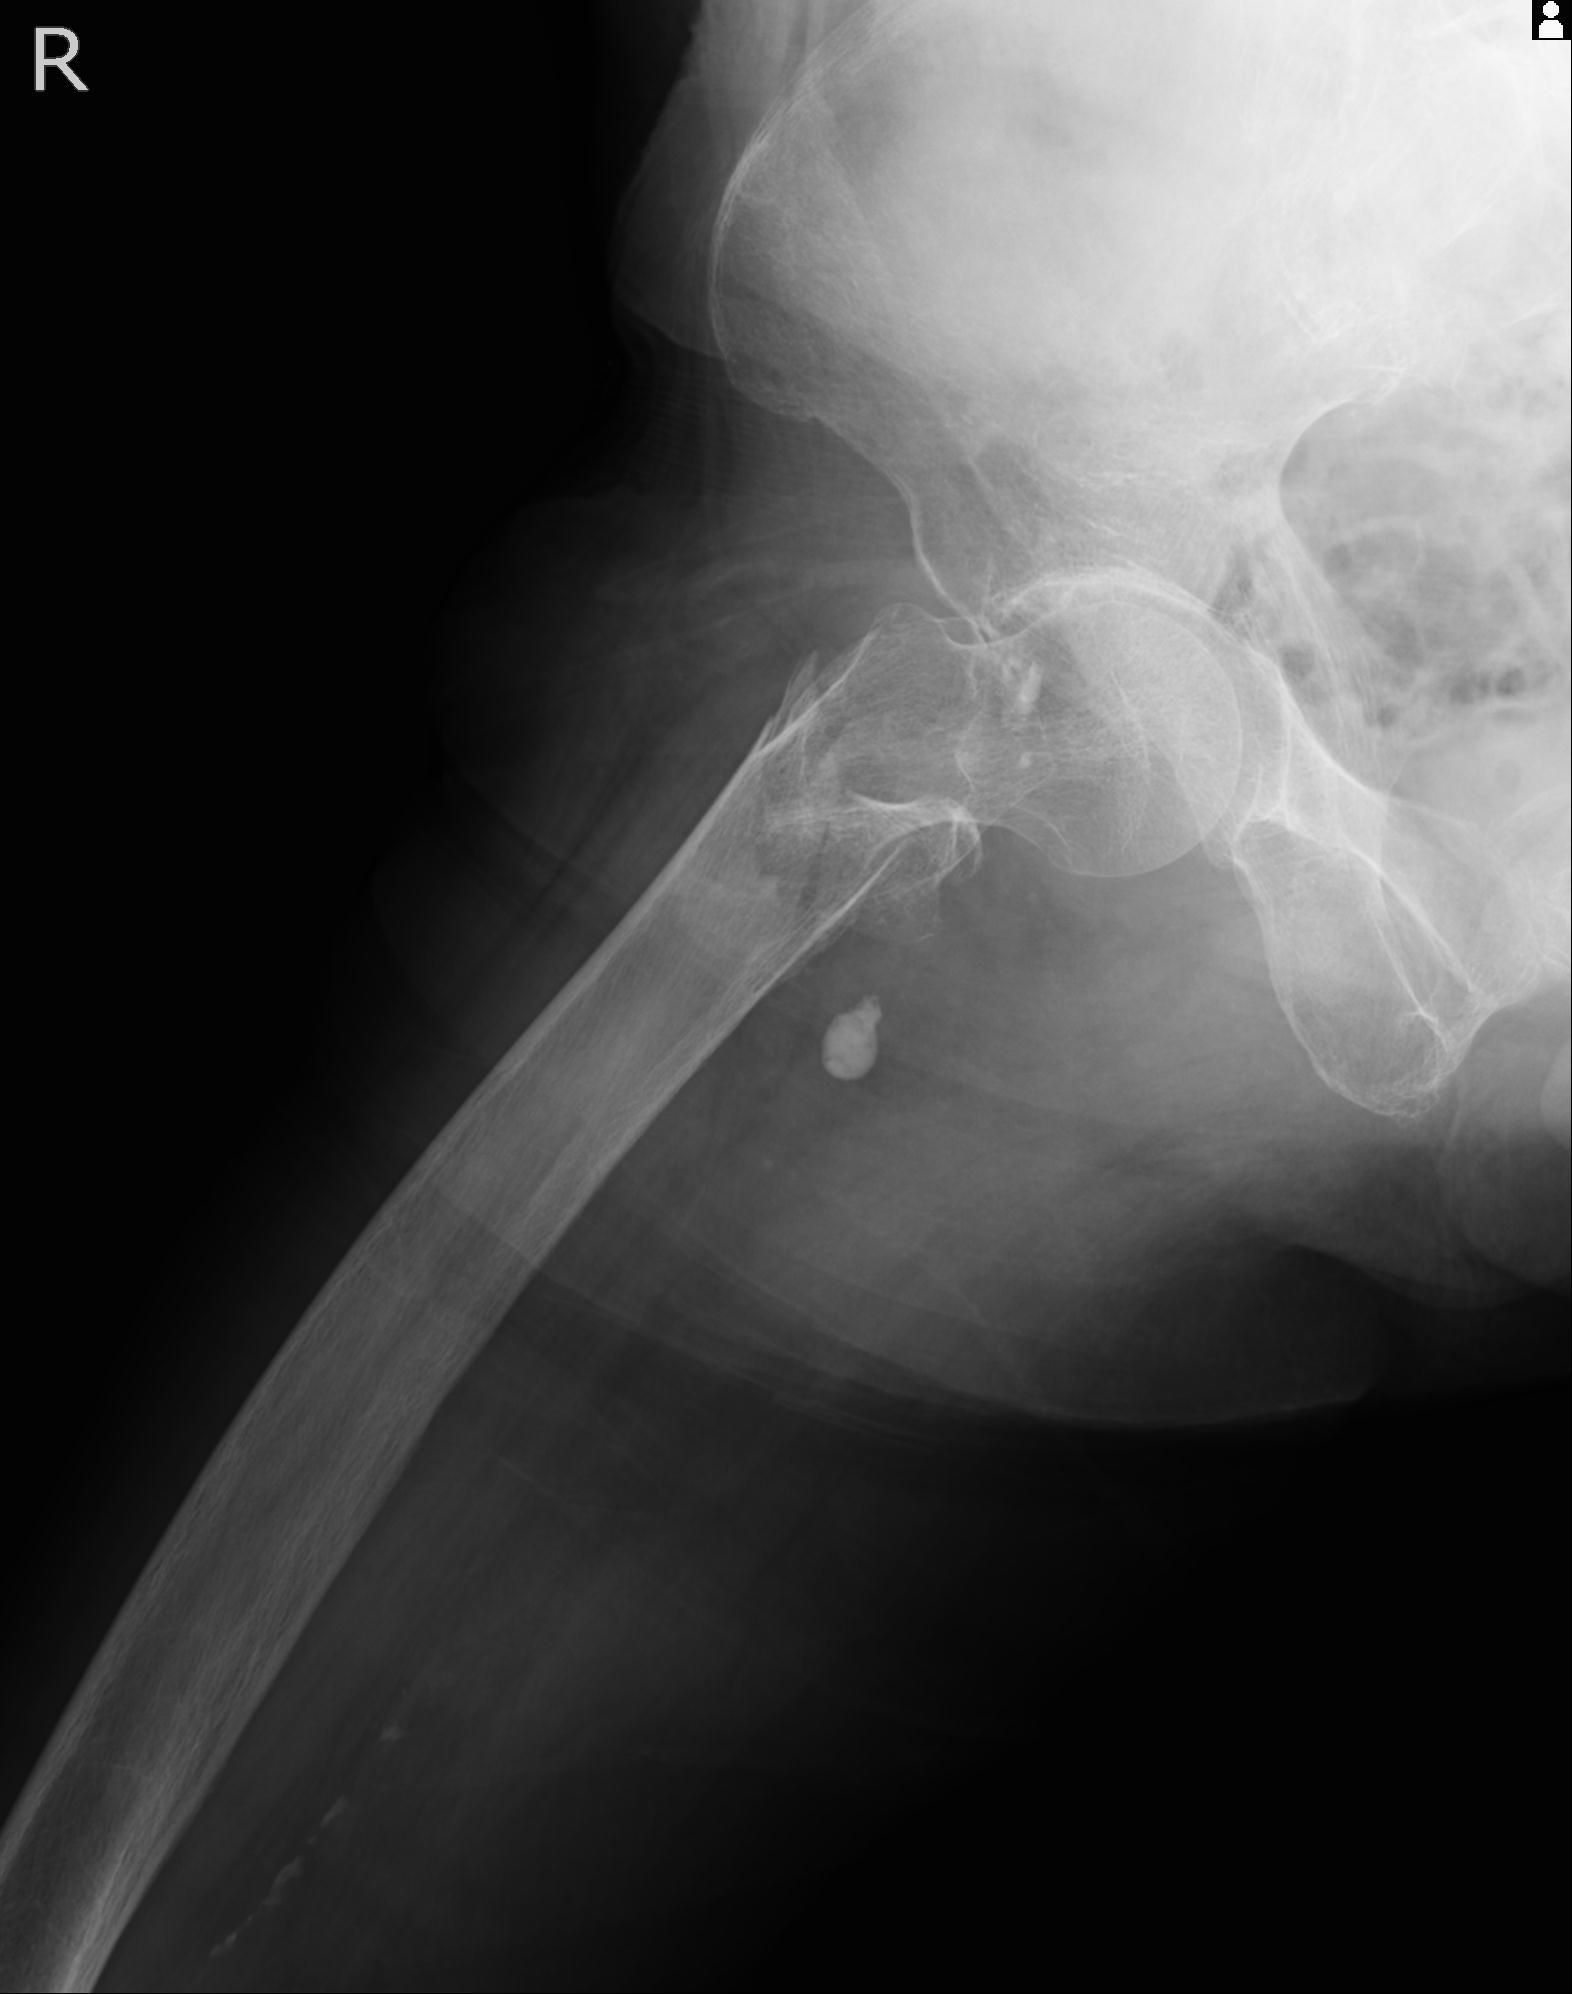

110286 2/17 股関節 2R 74歳女性 右人工骨頭